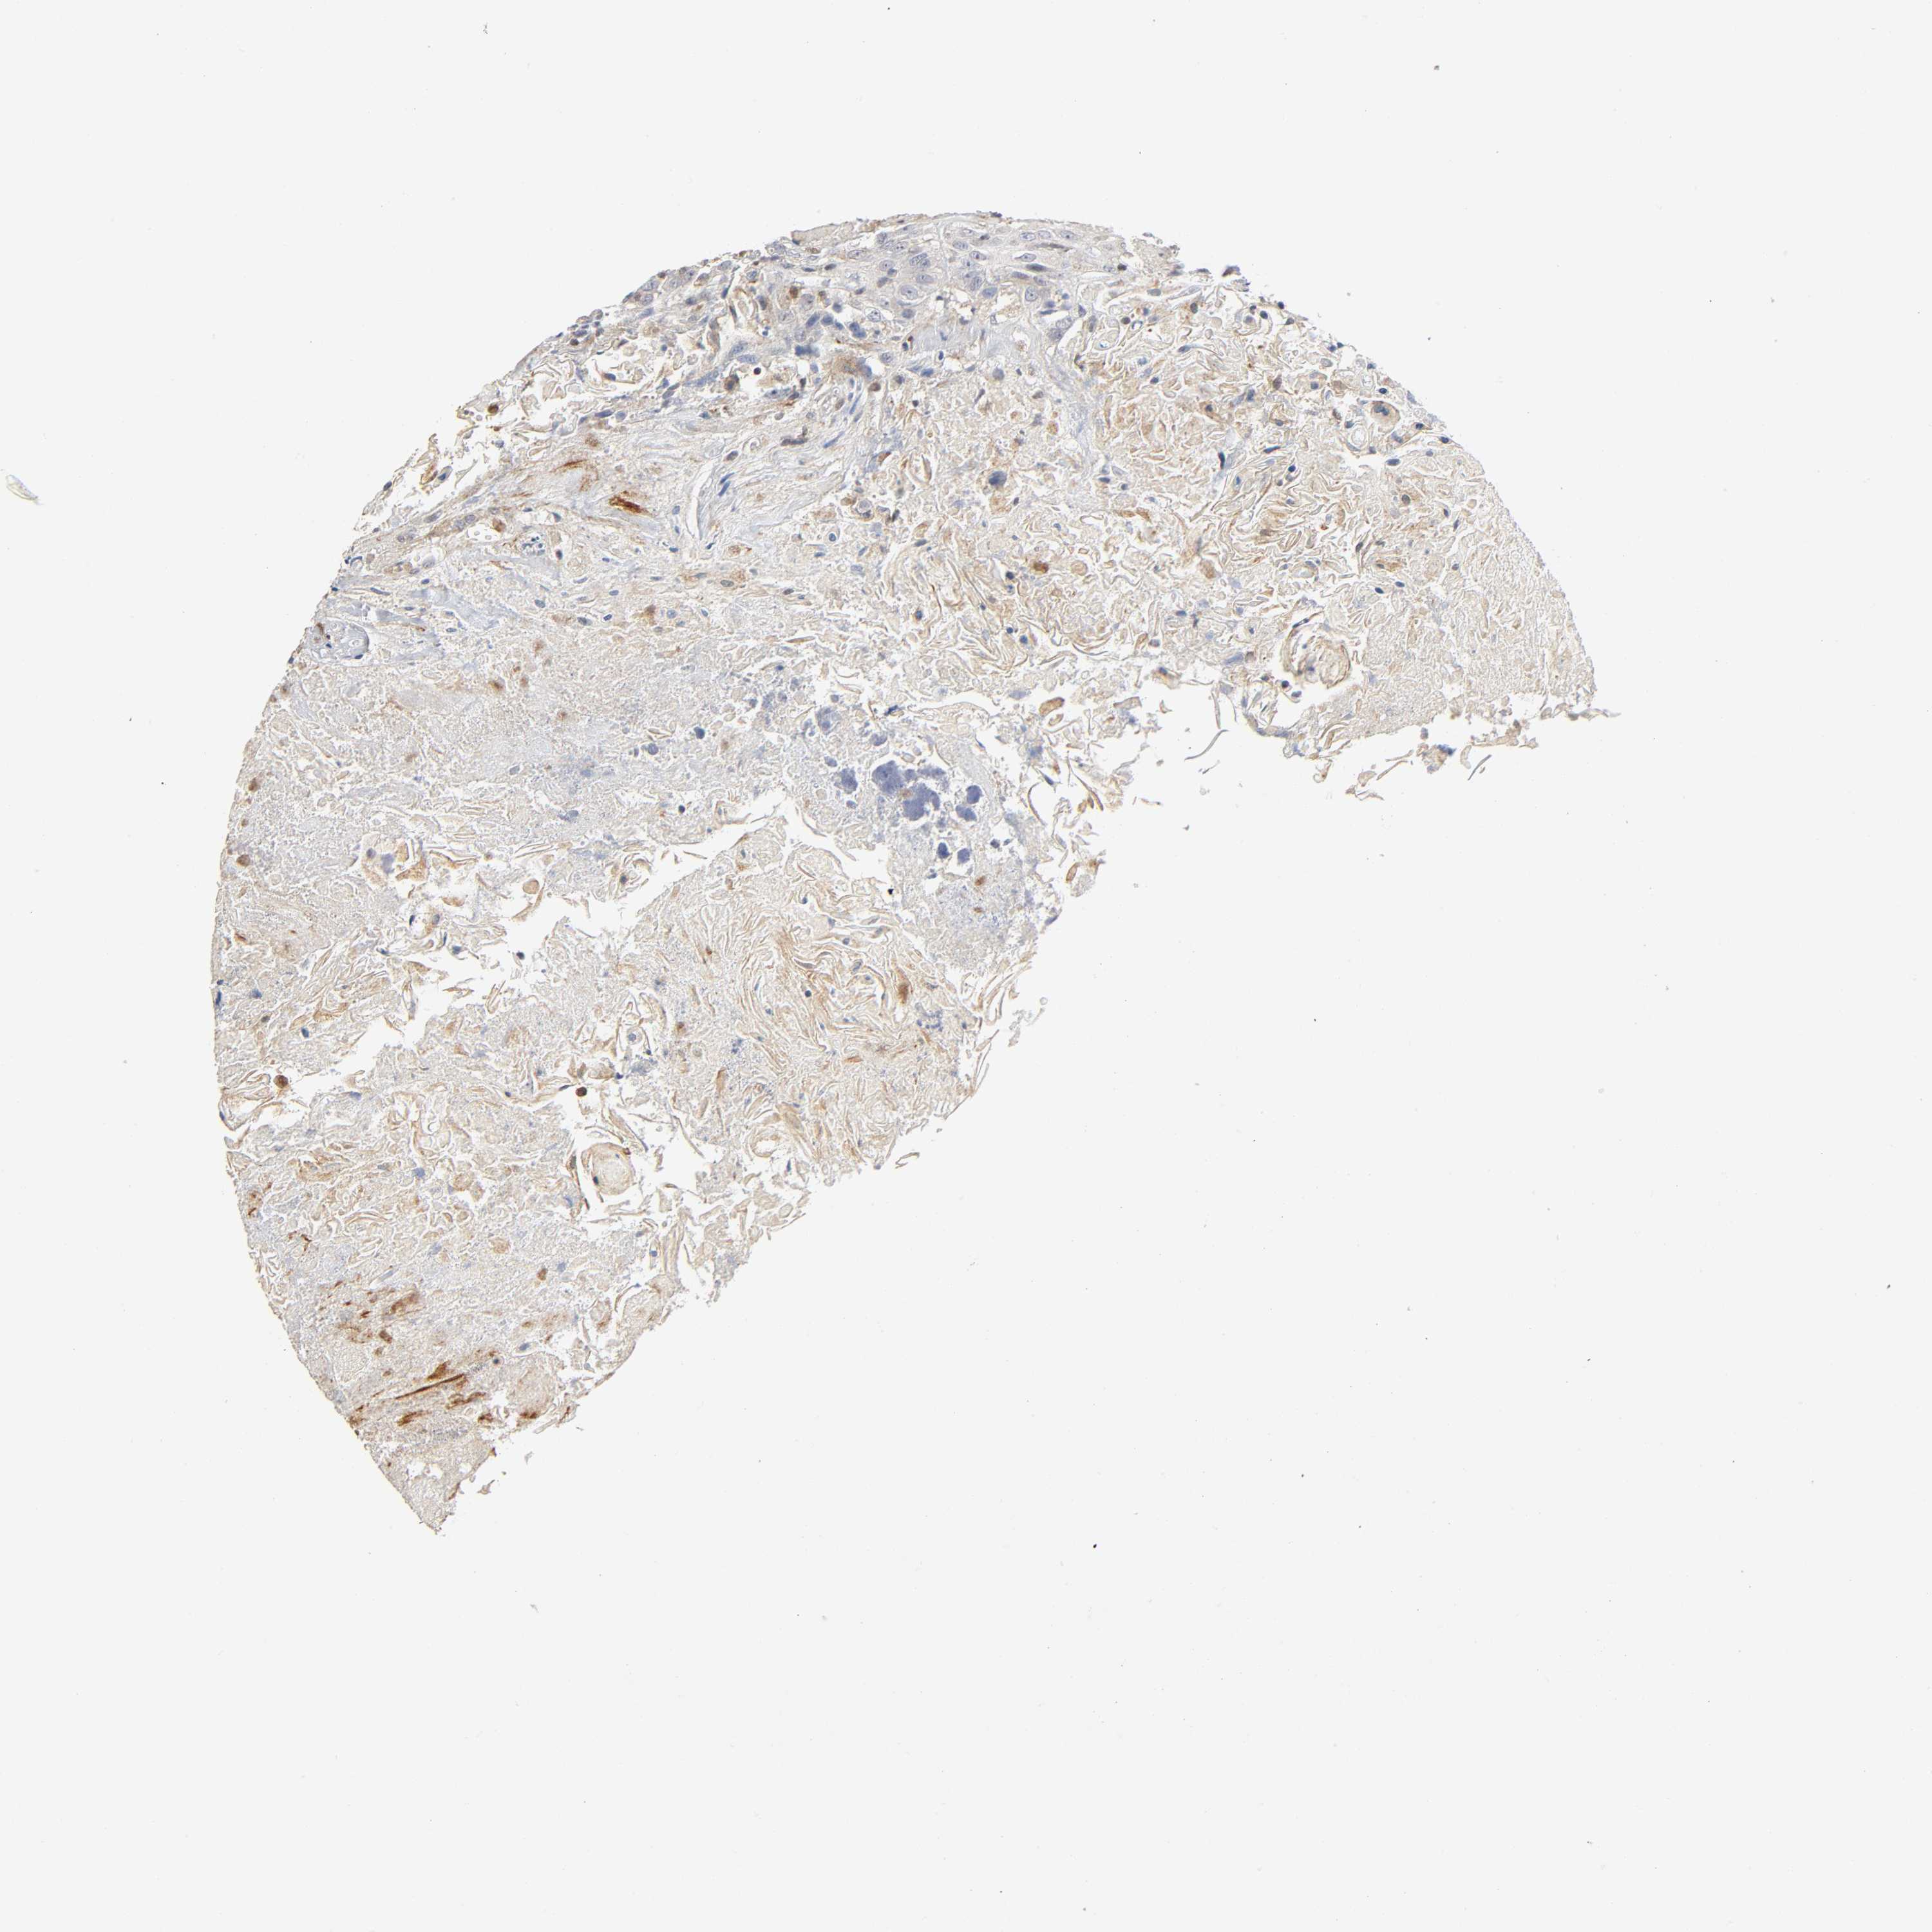

HEAD AND NECK CANCER - Protein expressioni

A mouse-over function shows sample information and annotation data. Click on an image to view it in a full screen mode. Samples can be filtered based on level of antibody staining by selecting one or several of the following categories: high, medium, low and not detected. The assay and annotation is described here.

Antibody stainingi

Antibody staining in the annotated cell types in the current human tissue is reported as not detected, low, medium, or high, based on conventional immunohistochemistry profiling in selected tissues. This score is based on the combination of the staining intensity and fraction of stained cells.

Each image is clickable and will lead to virtual microscopy that enables deeper exploration of all samples and also displays staining intensity scores, fraction scores and subcellular localization as well as patient and tissue information for each sample.

Antibody HPA001473

Antibody HPA046488

Antibody CAB004348

Staining

High

Medium

Low

Not detected

Intensity

Strong

Moderate

Weak

Negative

Quantity

>75%

75%-25%

<25%

None

Location

Nuclear

Cytoplasmic/membranous

Cytoplasmic/membranous,nuclear

Squamous cell carcinoma, NOS

Squamous cell carcinoma, metastatic, NOS

Adenocarcinoma, NOS

Neoplasm, malignant, NOS

Carcinoma, NOS